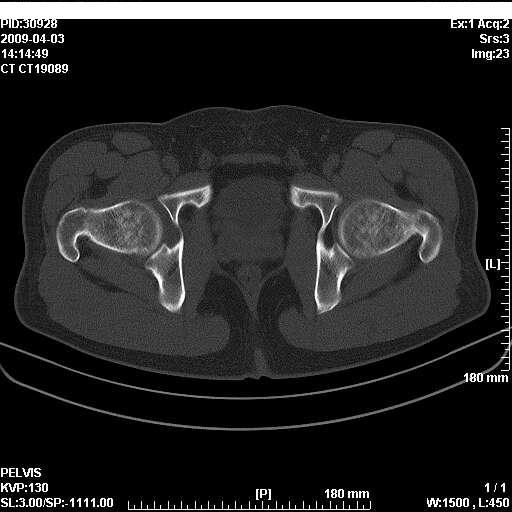

以下是引用随光逐影在2009-4-4 15:13:00的发言:[br]考虑双侧股骨头无菌性坏死;建议行mri检查进一步明确诊断。

以下是引用余辉在2009-4-4 14:22:00的发言:[br]双侧髋关节诸构成骨未见明显异常.必要时mr检查[br]患者症状已有两年,可能要同时从其他方面找原因,个人觉得不排除双侧骶髂关节有问题,建议ct检查